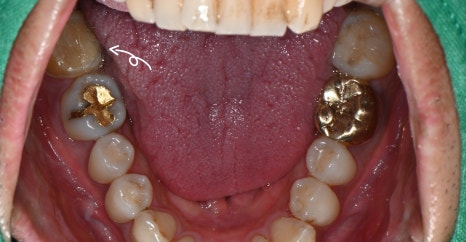

Panoramic and intraoral photos taken at the first visit

A male patient in his 30s visited us with the symptom, “My lower right molar feels sensitive when I drink cold water.”

He did not have severe pain, but repeated discomfort in daily life led him to want an accurate diagnosis.